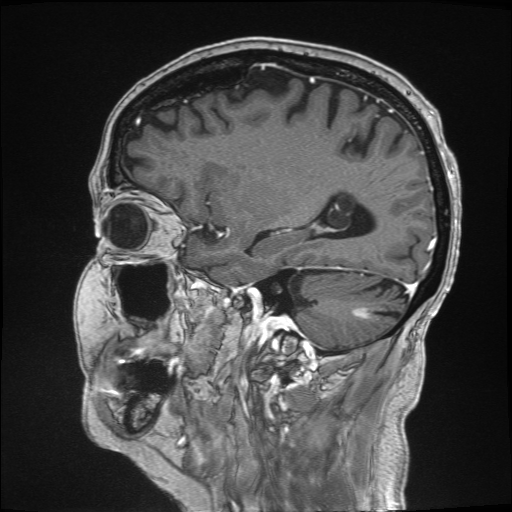

4.3 Evaluation on real low-dose images

Refer to captionRefer to caption𝐱PCsubscript𝐱PC\mathbf{x}_{\mathrm{PC}}bold_x start_POSTSUBSCRIPT roman_PC end_POSTSUBSCRIPTRefer to captionRefer to caption𝐱LDsubscript𝐱LD\mathbf{x}_{\mathrm{LD}}bold_x start_POSTSUBSCRIPT roman_LD end_POSTSUBSCRIPTRefer to captionRefer to caption𝐱SDsubscript𝐱SD\mathbf{x}_{\mathrm{SD}}bold_x start_POSTSUBSCRIPT roman_SD end_POSTSUBSCRIPTRefer to captionRefer to captionAm-3D [14]Refer to captionRefer to captionPa-2.5D [8]Refer to captionRefer to caption𝐱~SDsubscript~𝐱SD\tilde{\mathbf{x}}_{\mathrm{SD}}over~ start_ARG bold_x end_ARG start_POSTSUBSCRIPT roman_SD end_POSTSUBSCRIPT (ours)ptPhilips Achieva 3TGadobutrol dLD=0.10subscript𝑑LD0.10d_{\mathrm{LD}}=0.10italic_d start_POSTSUBSCRIPT roman_LD end_POSTSUBSCRIPT = 0.10ptPhilips Ingenia 1.5TGadoterate dLD=0.33subscript𝑑LD0.33d_{\mathrm{LD}}=0.33italic_d start_POSTSUBSCRIPT roman_LD end_POSTSUBSCRIPT = 0.33Refer to captionRefer to caption𝐱PCsubscript𝐱PC\mathbf{x}_{\mathrm{PC}}bold_x start_POSTSUBSCRIPT roman_PC end_POSTSUBSCRIPTRefer to captionRefer to caption𝐱LDsubscript𝐱LD\mathbf{x}_{\mathrm{LD}}bold_x start_POSTSUBSCRIPT roman_LD end_POSTSUBSCRIPTRefer to captionRefer to caption𝐱SDsubscript𝐱SD\mathbf{x}_{\mathrm{SD}}bold_x start_POSTSUBSCRIPT roman_SD end_POSTSUBSCRIPTRefer to captionRefer to captionAm-3D [14]Refer to captionRefer to captionPa-2.5D [8]Refer to captionRefer to caption𝐱~SDsubscript~𝐱SD\tilde{\mathbf{x}}_{\mathrm{SD}}over~ start_ARG bold_x end_ARG start_POSTSUBSCRIPT roman_SD end_POSTSUBSCRIPT (ours)ptPhilips Achieva 3TGadobutrol dLD=0.10subscript𝑑LD0.10d_{\mathrm{LD}}=0.10italic_d start_POSTSUBSCRIPT roman_LD end_POSTSUBSCRIPT = 0.10ptPhilips Ingenia 1.5TGadoterate dLD=0.33subscript𝑑LD0.33d_{\mathrm{LD}}=0.33italic_d start_POSTSUBSCRIPT roman_LD end_POSTSUBSCRIPT = 0.33Refer to captionRefer to caption𝐱PCsubscript𝐱PC\mathbf{x}_{\mathrm{PC}}bold_x start_POSTSUBSCRIPT roman_PC end_POSTSUBSCRIPTRefer to captionRefer to caption𝐱LDsubscript𝐱LD\mathbf{x}_{\mathrm{LD}}bold_x start_POSTSUBSCRIPT roman_LD end_POSTSUBSCRIPTRefer to captionRefer to caption𝐱SDsubscript𝐱SD\mathbf{x}_{\mathrm{SD}}bold_x start_POSTSUBSCRIPT roman_SD end_POSTSUBSCRIPTRefer to captionRefer to captionAm-3D [14]Refer to captionRefer to captionPa-2.5D [8]Refer to captionRefer to caption𝐱~SDsubscript~𝐱SD\tilde{\mathbf{x}}_{\mathrm{SD}}over~ start_ARG bold_x end_ARG start_POSTSUBSCRIPT roman_SD end_POSTSUBSCRIPT (ours)ptPhilips Achieva 3TGadobutrol dLD=0.10subscript𝑑LD0.10d_{\mathrm{LD}}=0.10italic_d start_POSTSUBSCRIPT roman_LD end_POSTSUBSCRIPT = 0.10ptPhilips Ingenia 1.5TGadoterate dLD=0.33subscript𝑑LD0.33d_{\mathrm{LD}}=0.33italic_d start_POSTSUBSCRIPT roman_LD end_POSTSUBSCRIPT = 0.33Refer to captionRefer to caption𝐱PCsubscript𝐱PC\mathbf{x}_{\mathrm{PC}}bold_x start_POSTSUBSCRIPT roman_PC end_POSTSUBSCRIPTRefer to captionRefer to caption𝐱LDsubscript𝐱LD\mathbf{x}_{\mathrm{LD}}bold_x start_POSTSUBSCRIPT roman_LD end_POSTSUBSCRIPTRefer to captionRefer to caption𝐱SDsubscript𝐱SD\mathbf{x}_{\mathrm{SD}}bold_x start_POSTSUBSCRIPT roman_SD end_POSTSUBSCRIPTRefer to captionRefer to captionAm-3D [14]Refer to captionRefer to captionPa-2.5D [8]Refer to captionRefer to caption𝐱~SDsubscript~𝐱SD\tilde{\mathbf{x}}_{\mathrm{SD}}over~ start_ARG bold_x end_ARG start_POSTSUBSCRIPT roman_SD end_POSTSUBSCRIPT (ours)ptPhilips Achieva 3TGadobutrol dLD=0.10subscript𝑑LD0.10d_{\mathrm{LD}}=0.10italic_d start_POSTSUBSCRIPT roman_LD end_POSTSUBSCRIPT = 0.10ptPhilips Ingenia 1.5TGadoterate dLD=0.33subscript𝑑LD0.33d_{\mathrm{LD}}=0.33italic_d start_POSTSUBSCRIPT roman_LD end_POSTSUBSCRIPT = 0.33Refer to captionRefer to caption𝐱PCsubscript𝐱PC\mathbf{x}_{\mathrm{PC}}bold_x start_POSTSUBSCRIPT roman_PC end_POSTSUBSCRIPTRefer to captionRefer to caption𝐱LDsubscript𝐱LD\mathbf{x}_{\mathrm{LD}}bold_x start_POSTSUBSCRIPT roman_LD end_POSTSUBSCRIPTRefer to captionRefer to caption𝐱SDsubscript𝐱SD\mathbf{x}_{\mathrm{SD}}bold_x start_POSTSUBSCRIPT roman_SD end_POSTSUBSCRIPTRefer to captionRefer to captionAm-3D [14]Refer to captionRefer to captionPa-2.5D [8]Refer to captionRefer to caption𝐱~SDsubscript~𝐱SD\tilde{\mathbf{x}}_{\mathrm{SD}}over~ start_ARG bold_x end_ARG start_POSTSUBSCRIPT roman_SD end_POSTSUBSCRIPT (ours)ptPhilips Achieva 3TGadobutrol dLD=0.10subscript𝑑LD0.10d_{\mathrm{LD}}=0.10italic_d start_POSTSUBSCRIPT roman_LD end_POSTSUBSCRIPT = 0.10ptPhilips Ingenia 1.5TGadoterate dLD=0.33subscript𝑑LD0.33d_{\mathrm{LD}}=0.33italic_d start_POSTSUBSCRIPT roman_LD end_POSTSUBSCRIPT = 0.33Refer to captionRefer to caption𝐱PCsubscript𝐱PC\mathbf{x}_{\mathrm{PC}}bold_x start_POSTSUBSCRIPT roman_PC end_POSTSUBSCRIPTRefer to captionRefer to caption𝐱LDsubscript𝐱LD\mathbf{x}_{\mathrm{LD}}bold_x start_POSTSUBSCRIPT roman_LD end_POSTSUBSCRIPTRefer to captionRefer to caption𝐱SDsubscript𝐱SD\mathbf{x}_{\mathrm{SD}}bold_x start_POSTSUBSCRIPT roman_SD end_POSTSUBSCRIPTRefer to captionRefer to captionAm-3D [14]Refer to captionRefer to captionPa-2.5D [8]Refer to captionRefer to caption𝐱~SDsubscript~𝐱SD\tilde{\mathbf{x}}_{\mathrm{SD}}over~ start_ARG bold_x end_ARG start_POSTSUBSCRIPT roman_SD end_POSTSUBSCRIPT (ours)ptPhilips Achieva 3TGadobutrol dLD=0.10subscript𝑑LD0.10d_{\mathrm{LD}}=0.10italic_d start_POSTSUBSCRIPT roman_LD end_POSTSUBSCRIPT = 0.10ptPhilips Ingenia 1.5TGadoterate dLD=0.33subscript𝑑LD0.33d_{\mathrm{LD}}=0.33italic_d start_POSTSUBSCRIPT roman_LD end_POSTSUBSCRIPT = 0.33Refer to captionRefer to caption𝐱PCsubscript𝐱PC\mathbf{x}_{\mathrm{PC}}bold_x start_POSTSUBSCRIPT roman_PC end_POSTSUBSCRIPTRefer to captionRefer to caption𝐱LDsubscript𝐱LD\mathbf{x}_{\mathrm{LD}}bold_x start_POSTSUBSCRIPT roman_LD end_POSTSUBSCRIPTRefer to captionRefer to caption𝐱SDsubscript𝐱SD\mathbf{x}_{\mathrm{SD}}bold_x start_POSTSUBSCRIPT roman_SD end_POSTSUBSCRIPTRefer to captionRefer to captionAm-3D [14]Refer to captionRefer to captionPa-2.5D [8]Refer to captionRefer to caption𝐱~SDsubscript~𝐱SD\tilde{\mathbf{x}}_{\mathrm{SD}}over~ start_ARG bold_x end_ARG start_POSTSUBSCRIPT roman_SD end_POSTSUBSCRIPT (ours)ptPhilips Achieva 3TGadobutrol dLD=0.10subscript𝑑LD0.10d_{\mathrm{LD}}=0.10italic_d start_POSTSUBSCRIPT roman_LD end_POSTSUBSCRIPT = 0.10ptPhilips Ingenia 1.5TGadoterate dLD=0.33subscript𝑑LD0.33d_{\mathrm{LD}}=0.33italic_d start_POSTSUBSCRIPT roman_LD end_POSTSUBSCRIPT = 0.33

Figure 6: Qualitative evaluation on the RLS dataset. The top row depicts a 33%percent3333\%33 % low-dose sample, where the yellow zoom highlights the lesion. The bottom row shows a case with a 10%percent1010\%10 % real low-dose image and the lesion is marked by the yellow circles.

Next, Am-3D, Pa-2.5D, and our approach trained on the RLD dataset are evaluated on the 77777777 RLD test images. Here, ADC images are additionally fed into Am-3D as required [14].

A qualitative comparison of RLD test samples is shown in Figure 6. The required skull stripping and non-linear intensity normalization of Am-3D are readily apparent. Thus, a quantitative comparison to the target 𝐱SDsubscript𝐱SD\mathbf{x}_{\mathrm{SD}}bold_x start_POSTSUBSCRIPT roman_SD end_POSTSUBSCRIPT is not reasonable. Nevertheless, the CE signal strength in pathological regions (highlighted by the yellow circles) is well visible despite too smooth output images. The internal morphology and the border delineation also exhibit blurring. Pa-2.5D yields better image quality but the contrast strength in pathological regions is not well captured. In particular, the contrast signal overshoots for the 33%percent3333\%33 % low-dose scan in the first row and undershoots for the 10%percent1010\%10 % scan at the bottom, although the training dataset contains low-dose images at both dose levels. Our approach yields the highest image quality and predicts the contrast enhancement more accurately due to the focus on the enhancement signal and the conditional embeddings. As a result, our approach generates CE images preserving the image quality of the inputs by avoiding the synthesis of anatomical or noise patterns.